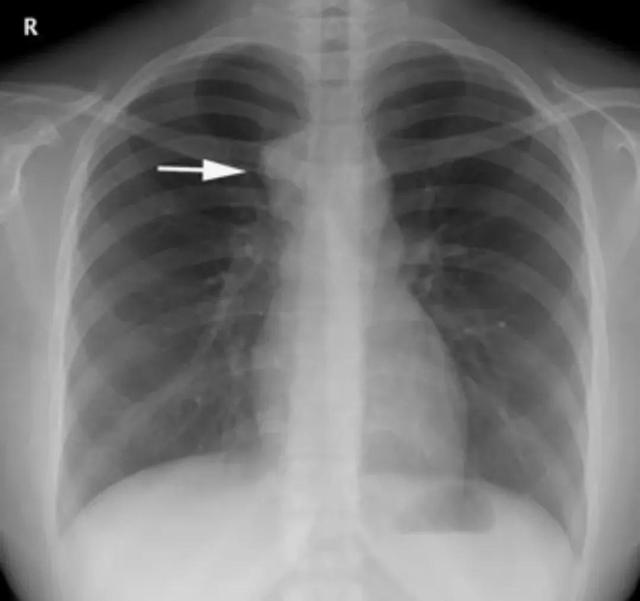

原发综合征 胸部正位片,左上肺可见斑片状模糊影,与左肺门增大软组织影相连接,呈典型“哑铃状”

(1)X线:原发病灶表现为云絮状或类圆形密度增高影,也可表现为肺段或肺叶范围的片状或大片状密度增高影,边缘模糊不清,可见于肺的任何部位,多见于上叶的下部或下叶上部靠近胸膜处。肺门或纵隔肿大淋巴结表现为突出于正常组织轮廓的结节影。自原发病灶引向肿大淋巴结的淋巴管炎,表现为一条或数条较模糊的条索状密度增高影。典型的原发综合征显示原发病灶、淋巴管炎与肿大肺门淋巴结连接在一起,形成“哑铃状”,但这种表现在临床上并不多见。有的患者原发病灶范围较大,常可掩盖淋巴管炎及淋巴结炎。

(2)CT:可清楚显示原发灶、引流的淋巴管炎及肿大的肺门淋巴结,也易于显示肿大淋巴结压迫支气管等所引起的肺叶或肺段不张,并能敏感发现原发灶邻近的胸膜改变。